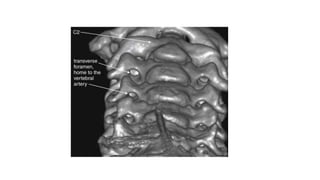

This three-dimensional CT model is oriented with the observer looking cephalad along the anterior

surface of the cervical spine. A series of holes perforating the transverse processes of each vertebra

can be seen—the transverse foramen.

This three-dimensional CTmodel is oriented with the observer looking cephalad along the anterior surface of the cervical spine. A series of holes perforating the transverse processes of each vertebra can be seen—the transverse foramen.